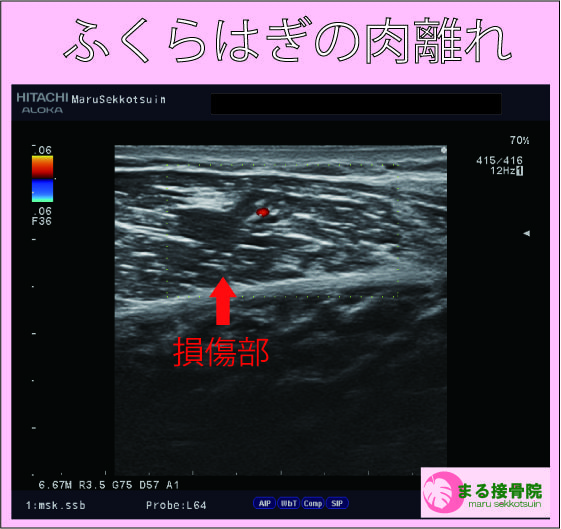

治療は、しっかり問診、触診、視診を行い、超音波画像診断装置で患部状態、深さ、広さをしっかり確認し、早期復帰、回復に向けて対処していきます。

ふくらはぎの肉離れ エコー画像.jpg

まずは患部の出血、腫れを最小限に抑え、周囲の筋肉も硬くならないようにし、タイミングを診てストレッチ、リハビリを行って参ります。